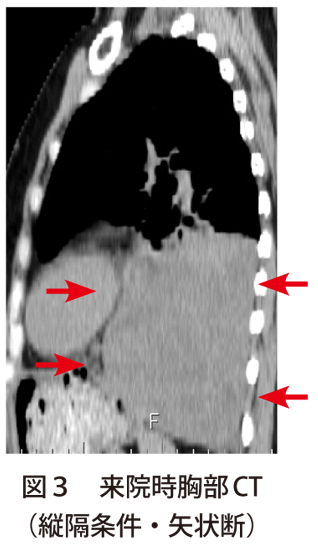

癒着浮腫と腫張の違い,癒着とは?貝癒着子宮癒着低置胎盤になる理由産婦人科専門医・周産期専門医からのメッセージ前置胎盤の診断前置胎盤癒着胎盤の記事一覧photo:01Placentalabruption【画像あり】胸部レントゲンで肺尖部に胸膜肥厚!これって異常?治療ガイド 胸膜の位置と構造レジデントノート 2014年5月号掲載【解答・解説】胸膜炎疑いで紹介受診した60歳代女性胸膜癒着術の手技、看護計画を解説【薬剤や副作用も併せてまとめました】2011年08月すべての幸せは対人関係からくる「話す自由」を尊重することがよりよい人間関係につながる~よい人間関係のつくり方~幸せな縦の関係建築主・設計者・工事施工者|基本とパターンで理解する三者の関係性相続関係説明図の概要と作成方法【パターン別見本付】1 労働関係とはSN6人物相関図